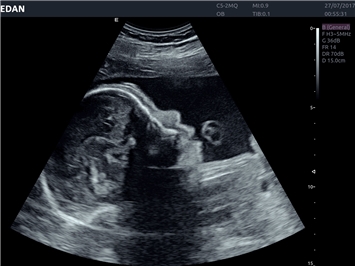

EDAN Acclarix LX4 представляет собой инновационную ультразвуковую систему, построенную на усовершенствованной платформе Acclarix. Сочетание высокого качества визуализации с интеллектуальным рабочим процессом делает эту систему оптимальным выбором для клиник, ценящих эффективность и экономичность.

• Акушерства и гинекологии

• Автоматизированные измерения в акушерстве

• 3D/4D-визуализация с автоматическим редактированием объема (eFace)